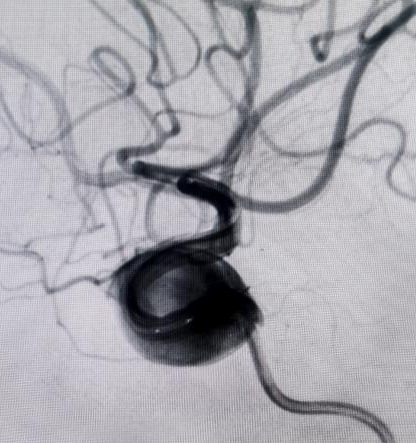

对于非责任动脉瘤的处理,医生们更是展现出专业与耐心。9个月前,患者动脉瘤破裂出血,当时造影发现2处动脉瘤,术中优先处理责任动脉瘤,待患者身体恢复后择期处理非责任动脉瘤。此次处理非责任动脉瘤,手术中造影,发现责任动脉瘤栓塞术后复发(3月前复查尚无),医生们当机立断,同期处理两个动脉瘤,省钱的同时,也成功为患者解除隐患。